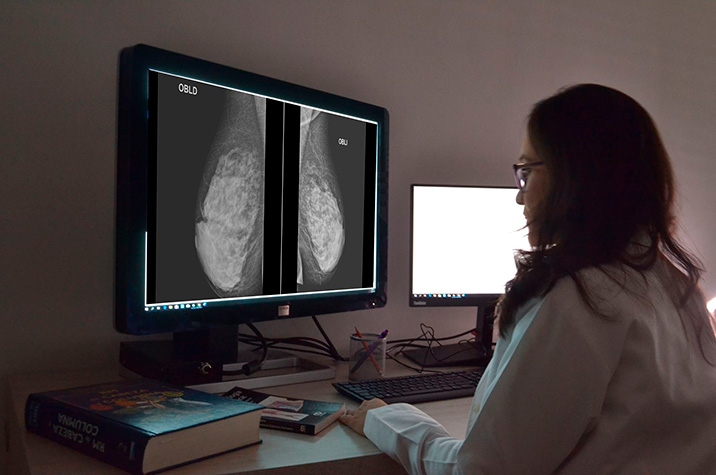

Asociación entre los resultados falsos positivos y el retorno a la mamografía de detección en la cohorte del Consorcio de Vigilancia del Cáncer de Mama

Después de un resultado falso positivo en una mamografía de rastreo, las mujeres tenían menos probabilidades de regresar al programa de detección, especialmente con recomendaciones de seguimiento a corto plazo o biopsia, lo que genera inquietud sobre la participación continua en la detección de rutina entre estas mujeres con mayor riesgo de cáncer de mama. Annals of Internal Medicine, 3 de septiembre de 2024.